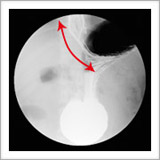

検査をすると、胃と食道の境目がゆるくて胃の一部が食道側に飛び出し(図1、図2)、一度胃に入ったバリウムが食道に戻ってきます(図3)

図1 |

| 胃の粘膜が食道側に飛び出しています。 |